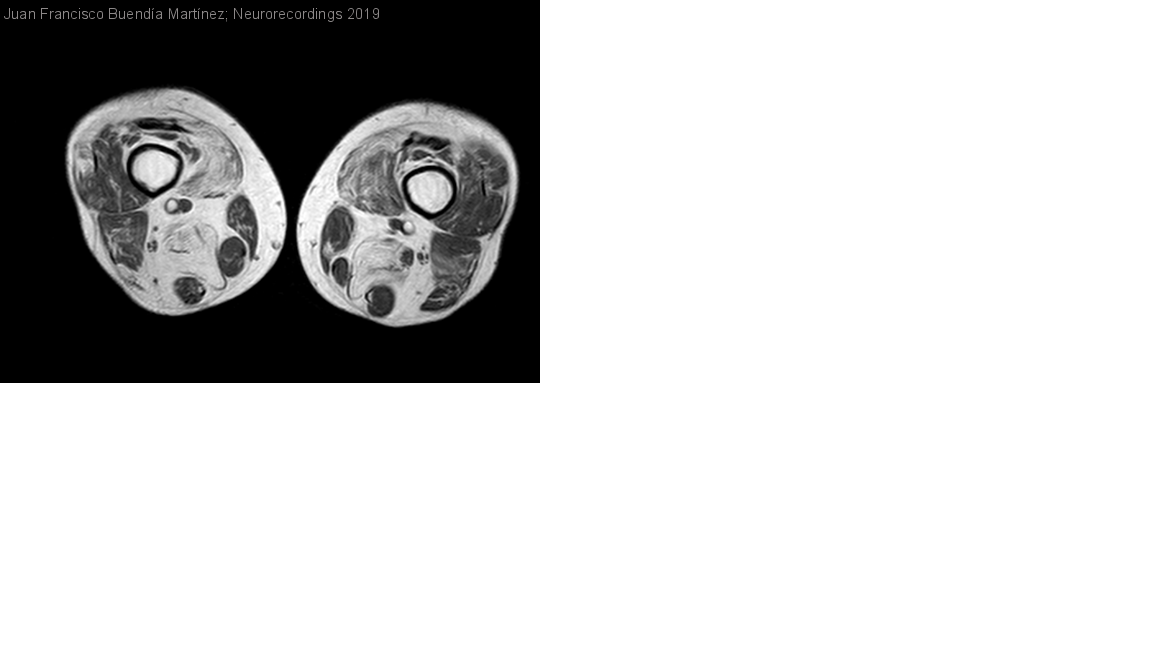

Diagnóstico final: miopatía asociada a ANO-5

Varón de 55 años sin antecedentes de interés. Niega consanguinidad, aunque sus padres comparten el segundo apellido y son naturales de un pequeño pueblo.

HiperCKemia detectada con 45 años de forma incidental, con niveles de CK...